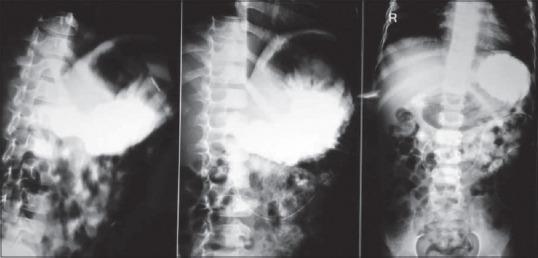

During 7 year period (2009-2016), 5 cases of GOO admitted to our hospital with a history of persistent vomiting. The vomiting used to occur 12-18 h after meal and vomitus contained foul-smelling undigested meal. There was no history of any caustic ingestion. Their age ranged from 2 to 10 years, with a median age of 6 years. Out of 5 cases, 2 were females and the rest were males. The diagnosis of idiopathic GOO was confirmed by history, clinical examination, contrast study, endoscopy, and endoscopic mucosal biopsy. The remarkable finding was the cicatrization causing stricture of the pyloric region in all cases. Out of 5 cases; we have done Heineke-Mikulicz pyloroplasty in 1 case, V-Y advancement antropyloroplasty in 2 cases and Kimura's Diamond-shaped Gastroduodenostomy in 2 cases. The length of the strictured segment determined the type of surgical procedure. All cases did well postoperatively with no mortality.

在7年期间(2009 - 2016年),我院收治了5例有持续性呕吐病史的胃出口梗阻病例。呕吐通常在餐后12 - 18小时发生,呕吐物含有恶臭的未消化食物。无任何腐蚀性物质摄入史。他们的年龄在2至10岁之间,中位年龄为6岁。5例中,2例为女性,其余为男性。通过病史、临床检查、造影检查、内镜检查及内镜黏膜活检确诊为特发性胃出口梗阻。显著发现是所有病例中瘢痕形成导致幽门区域狭窄。5例中,我们对1例行海涅克 - 米库利兹幽门成形术,2例行V - Y推进式胃幽门成形术,2例行木村菱形胃十二指肠吻合术。狭窄段的长度决定了手术方式。所有病例术后恢复良好,无死亡病例。